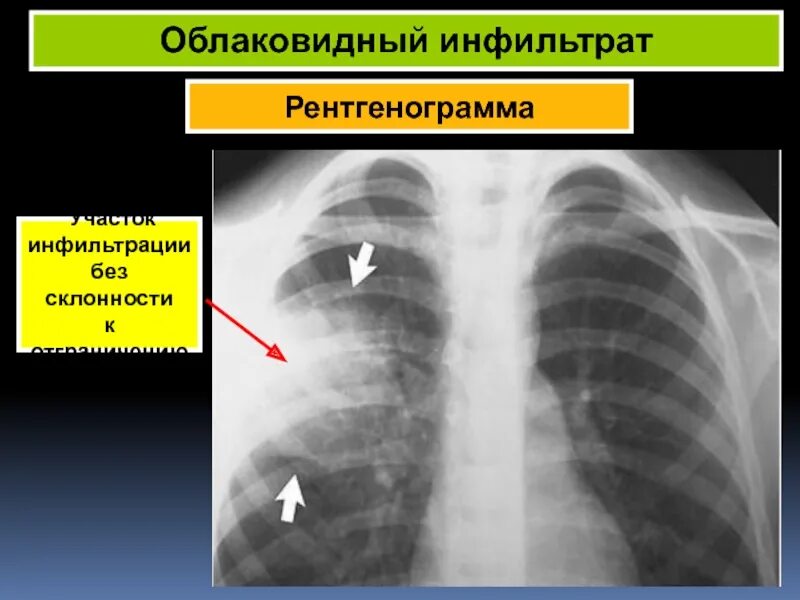

Без признаков инфильтрации